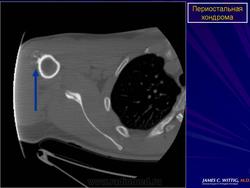

Хондрома периостальная.

Периостальная хондрома (син.: юкстакортикальная хондрома, паростальная хондрома редкая доброкачественная опухоль, состоящая из зрелой хрящевой ткани и расположенная над надкостницей. Обычно она разрушает наружную часть коркового слоя, но не прорастает в костно-мозговой канал. Мужчины болеют в два раза чаще женщин. Типичная локализация - проксимальный конец плечевой и бедренной кости дистальный конец бедренной кости, а также фаланги. В редких случаях одновременно поражается несколько костей. Периостальная хондрома обнаруживается большей частью в метафизарной части, лишь у 30 % больных поражаются диафизы. Опухоль достигает в среднем 2-3 см в диаметре. Она окружена зоной остеосклероза и сопровождается периостальным остеогенезом, так что на границе опухоли с костью образуется грушевидное углубление с четкими контурами. Под микроскопом периостальная хондрома имеет тонкие контуры, она как бы погружена в корковый слой и покрыта надкостницей, как тонкой скорлупой. На разрезе ее ткань синюшно-серая или белая, хрящевые элементы обладают дольчатым строением. Участки обызвествления имеют вид желтовато-белых вкраплений. Эта опухоль состоит из гиалинового хряща, дольки которого разделены фиброзными прослойками или костными балками, местами обызвествленными. Кое-где отмечается проникновение опухолевых клеток в костномозговой канал, на большем же протяжении внутренний контур образован компактной костью.

Дифференциальная диагностика представляет известные трудности в тех случаях, когда периостальная хондрома имеет сходство с юкстакортикальной хондросаркомой.